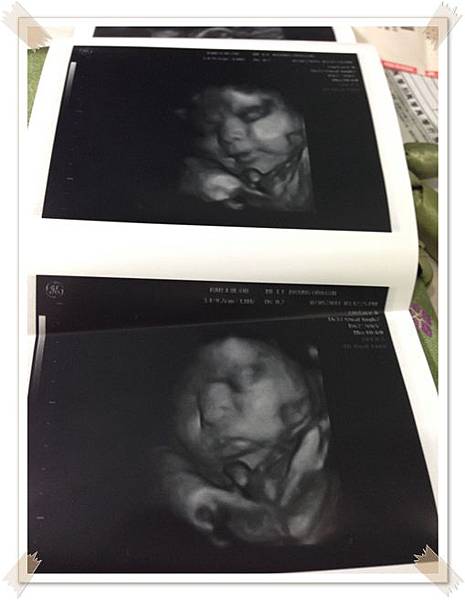

索性跑去社團媽媽很推薦的一家照4D很清楚的婦產科檢查

醫生挺有耐性的 , 大概照了10-20分鐘 ,也量了一下寶寶現在的體重大約2400g了

拿到照片好開心 ,因為第一次這麼清楚的看到寶寶的臉

醫生還說寶寶輪廓有爸爸的影子orz